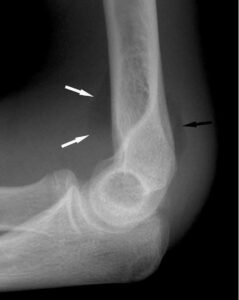

[toggle title=”Anterior Humeral Hat” state=”close”]

Lateral grafide humerus ön yüzeyine paralel ve bitişik çekilen çizgi kapitulumun 1/3 ortasından geçmelidir.

Bu hattın öne ya da arkaya yer değiştirmesi suprakondiler humerus kırığını destekler.

Aynı zamanda suprakondiler kırık hattıyla beraber posterior yağ yastıkçığı bulgusu da görülmekte

Bununla beraber kırık hattı ve posterior yağ yastıkçığı bulgusu da seçilmekte.